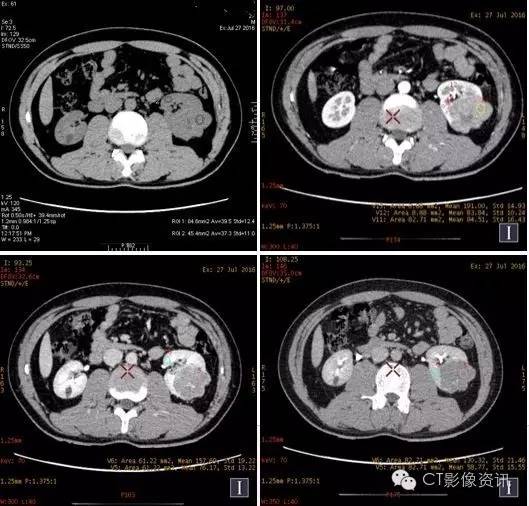

左肾病变位于左肾下极外后侧,与左肾髓质分界不清,向肾外生长并分叶。增强扫描左肾病变强化明显,皮质期病变强化程度低于左肾皮质,与左肾髓质相近,实质期及延迟期强化程度均显著低于左肾实质。

右肾病变位于右肾下极内后方,与肾实质分界清晰。增强扫描右肾病灶轻微强化,强化程度均低于右肾实质。

表一:双肾病灶及肾实质各期平扫及增强各期CT值测量结果

CT值单位:Hu 增强能谱扫描各期碘基物质图观察

此病例为年轻男性,体检时发现双肾病变。进行CT平扫及GSI增强扫描,从病变位置、形状、增强特点可考虑左右肾为不同病变。进行能谱数据进一步分析发现,左肾病变基物质碘含量及能谱曲线与左肾髓质相似(皮质期明显),右肾病变基物质碘含量及能谱曲线与肾实质及左肾病变存在较大差异,并且右肾病变在三期增强扫描能谱曲线均为“勺”状,提示其中含有脂肪成分。综合以上参数考虑,左肾病变与左肾髓质关系密切,右肾病变含脂肪成分,趋向于错构瘤。基本排除左右肾病变为同一病变。